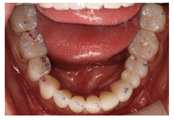

(1)面部检查:面部外形不对称,颏部居中,两侧口角高度不一致,面下1/3高度减小,两侧颧弓突度一致,下颌前突。中位笑线,上唇长度适中(图1)。(2)关节检查:颞颌关节:弹响(-),杂音(-),疼痛(-)。开口度正常,开口型有偏斜,肌肉触诊压痛:右侧上颌结节(+)、左侧上颌结节(++)、双侧翼内肌(+),其他肌肉及颞下颌关节区未诉异常,关节载荷实验无任何紧张和疼痛不适。(3)口内检查:上下颌牙中线较面中线向右偏斜,前后牙广泛不均匀磨耗,前牙磨耗后呈刃状;14、21、22、23及下颌牙唇颊侧颈部见釉质缺损,部分牙本质暴露,呈黄褐色,少量白垩色;44牙见开髓孔,表面暂封。12缺失,缺失牙间隙无。全口牙龈色形质未见异常,11牙、21牙唇侧牙龈龈缘高度不一致,21牙较11牙龈缘高约3mm。全口口腔卫生状况良好,菌斑、软垢少量,未及牙石及牙周袋。咬合检查:11-14牙与对颌牙反

,21牙与31、31牙对刃,左侧尖牙至前磨牙深覆盖,

曲线不平(图2,图3)。(4)影像学检查: